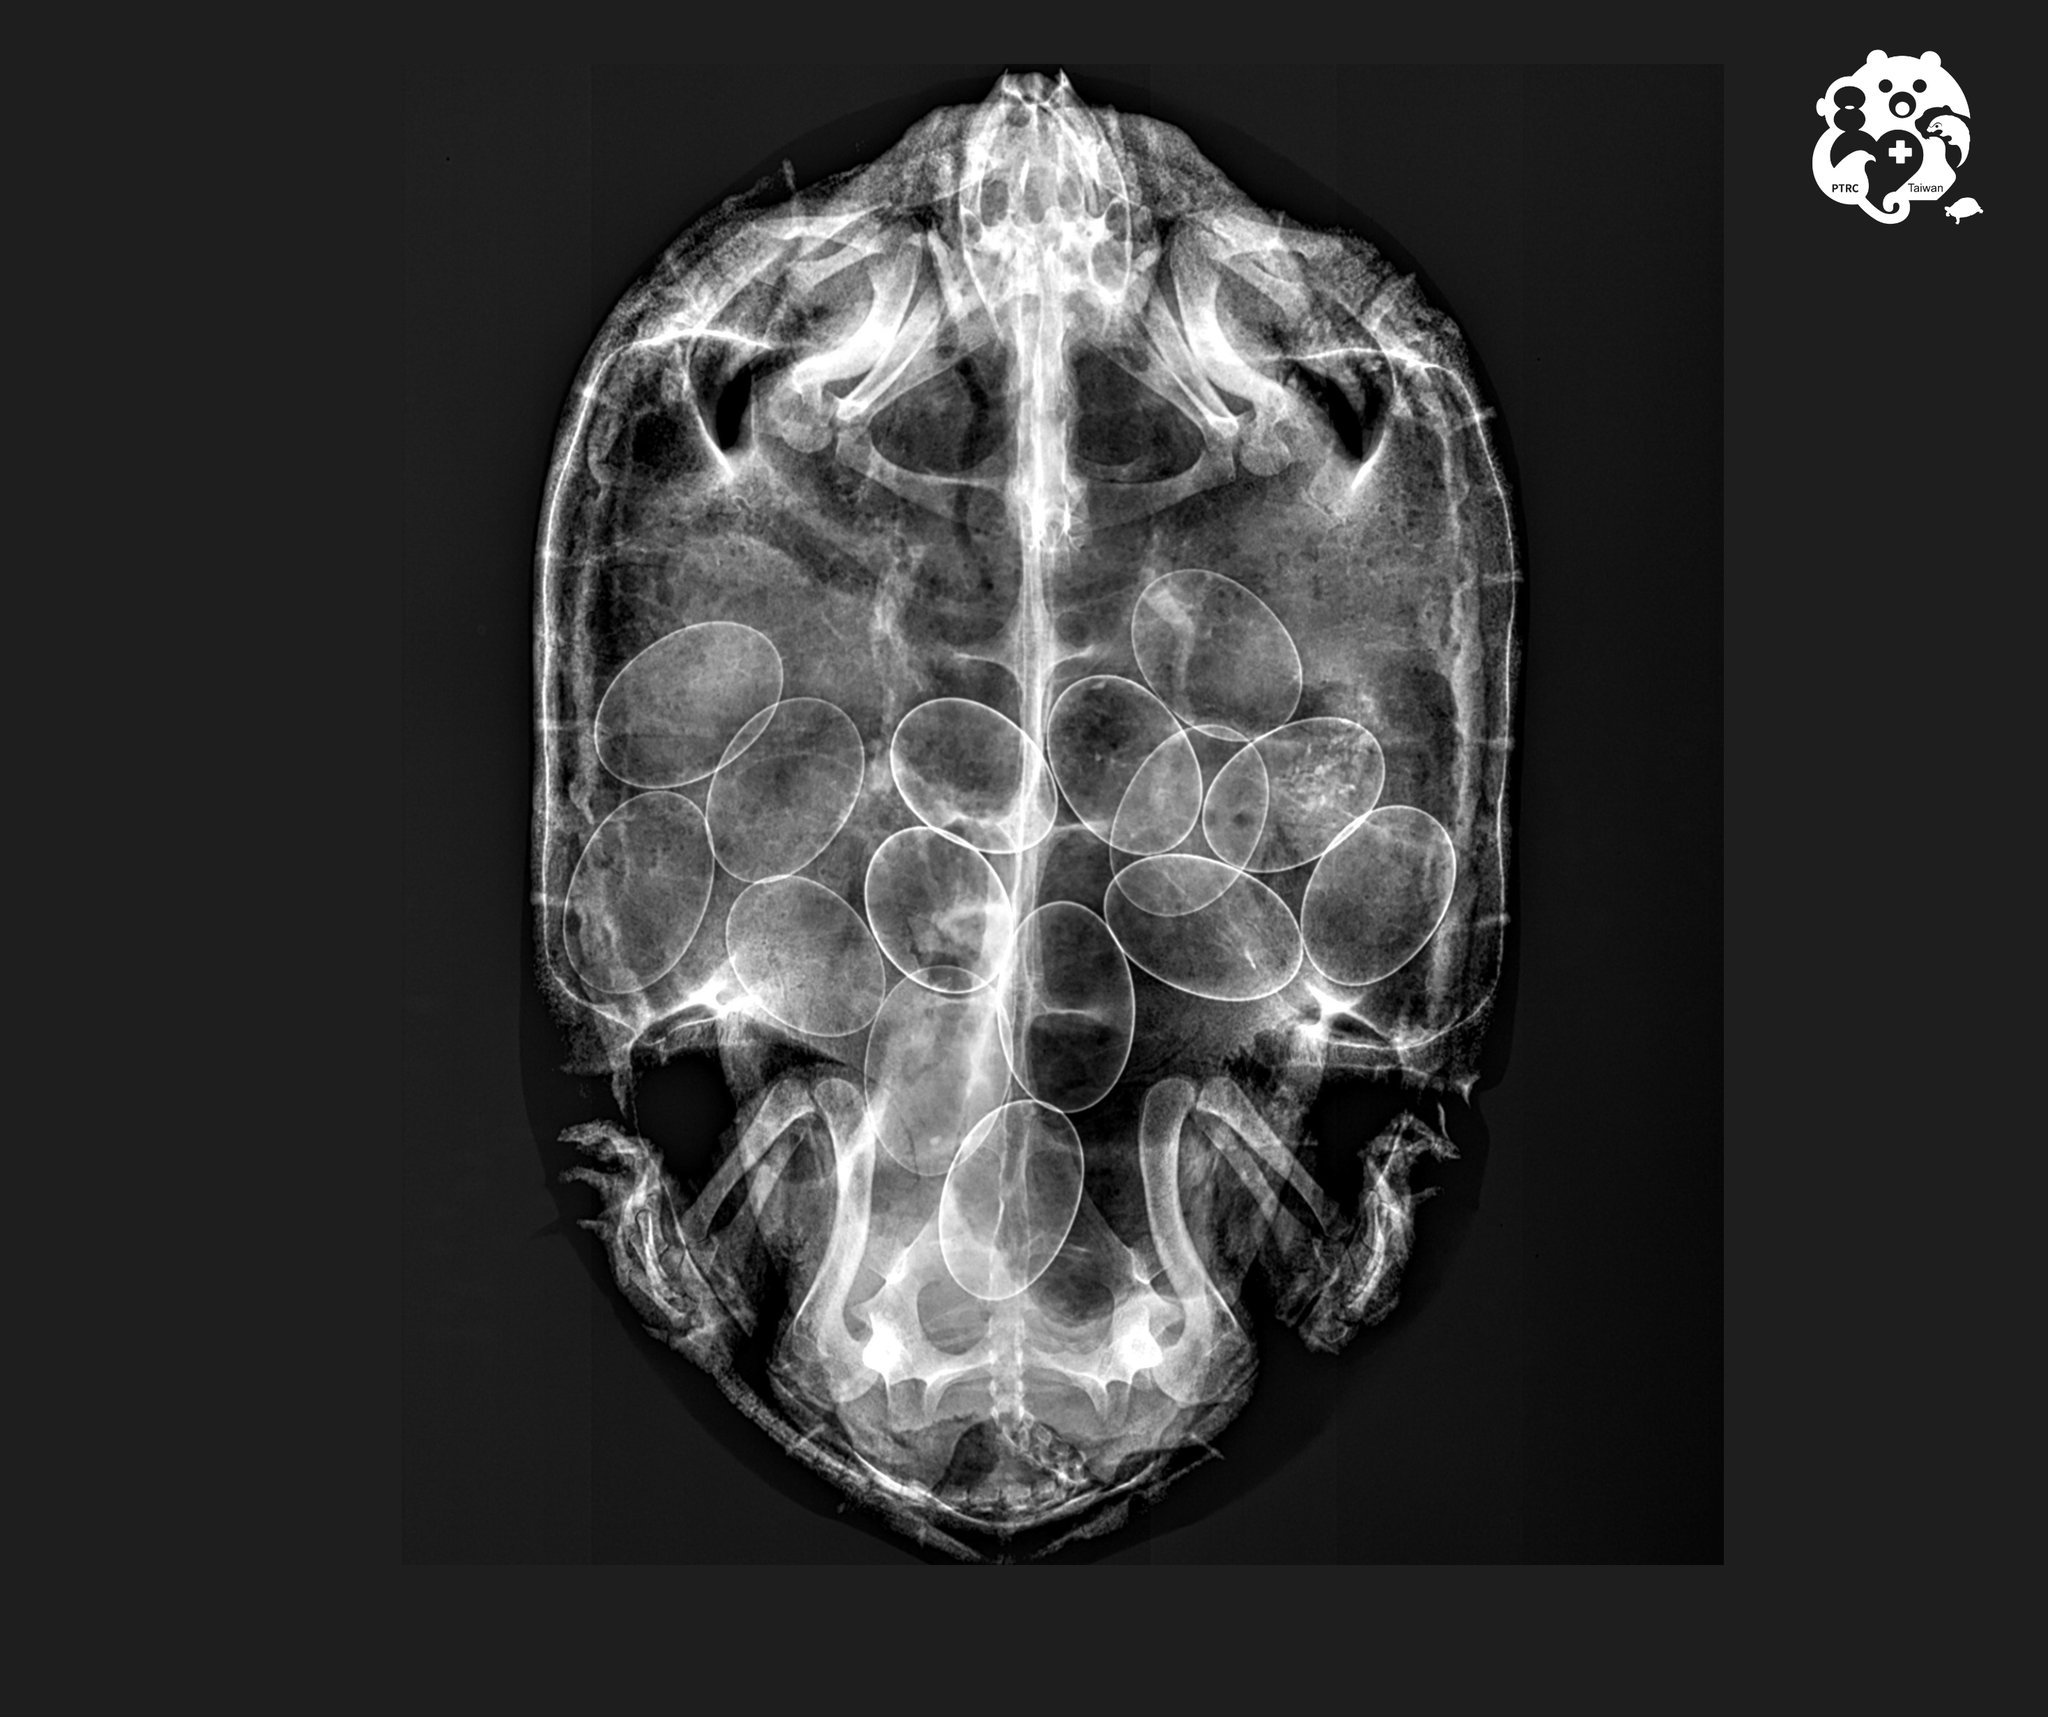

-【斑龜】

透過X光可以看到斑龜的肚子裡有非常多蛋![]() ,看來是一位準媽媽

,看來是一位準媽媽![]() ~

~